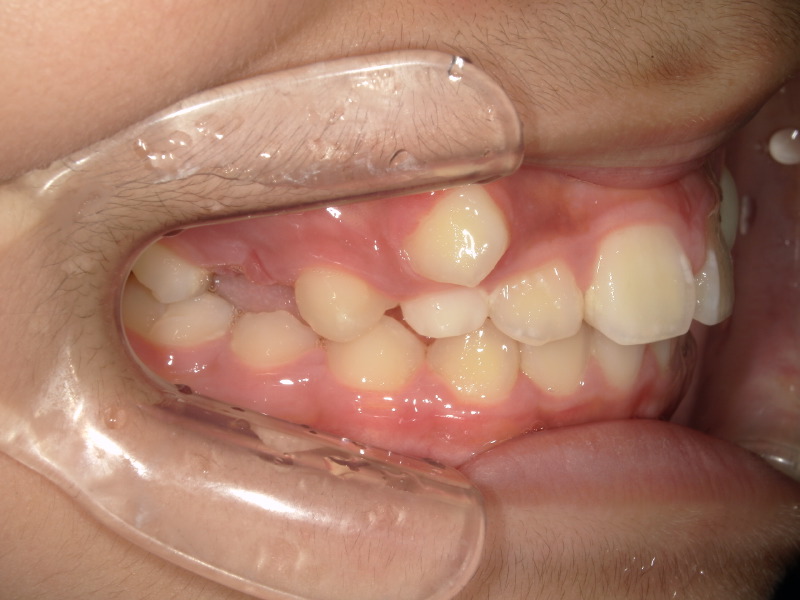

この男の子の主訴にもある八重歯、この歯は大体9ー10歳頃に生え変わりが起こる歯です。

写真でもあるように唇側の歯茎から出てきており、大きさもあるので顎のアーチの中には入らなさそうです。

このまま放置しているとこの歯は唇側に留まってしまい、いわゆる八重歯と呼ばれる歯になります。

アクティビティーも順調に進み、次は八重歯の歯を綺麗に入れるために装置を併用することになりました。